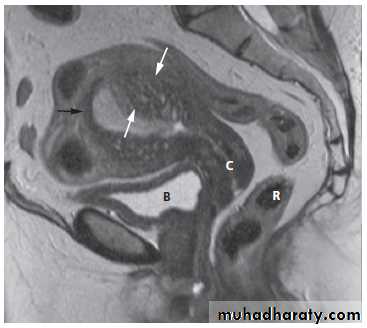

Magnetic resonance imagingPelvic anatomy is very well demonstrated because of the excellent soft tissue contrast afforded by MRI. Images are usually taken in the axial, coronal and sagittal planes . T2-weighted sagittal images show the vagina and cervix in continuity with the body of the uterus.

The zonal anatomy of the uterus is best demonstrated on T2-weighted images, with the endometrium having a high signal intensity, the adjacent inner myometrium (junctional zone) a low signal intensity, and the myometrium an intermediate signal intensity .

MRI may be used to further characterize indeterminate masses as benign or malignant prior to deciding on patient management. With disseminated malignancy, deposits within the omentum and ascites may be visible .

At CT fibroids are usually the same density as the adjacent myometrium. MRI can readily identify fibroids as they typically have a different signal characteristic from the normal uterus .

On MRI, there is focal or diffuse thickening of the junctional zone and, in some cases, multiple bright projections are seen extending from the endometrium into the myometrium .